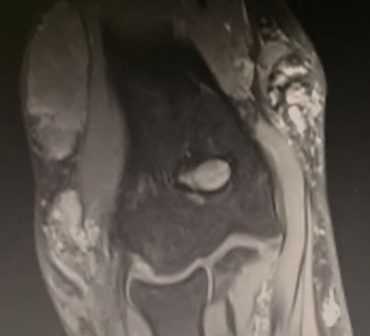

(Справа) На фронтальной MPT Т1ВИ визуализируется дополнительная надблоково-локтевая мышца, медиальнее локтевого отростка.